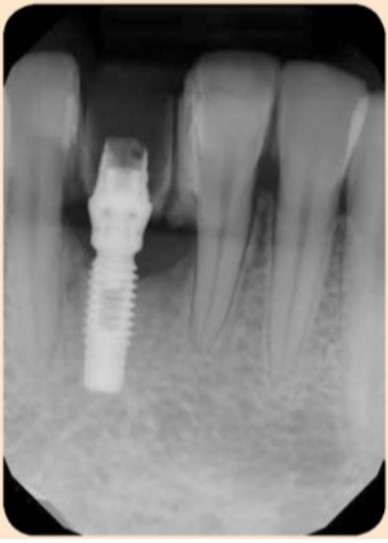

Ren của implant bị lộ và bị phủ bởi mảng bám và vôi răng, cũng quan sát được trên phim X-quang (hình dưới đây).

Tiêu mào xương quanh implant ở phía gần của implant #41. Chú ý có thể nhìn thấy vôi răng trên phim X- quang.